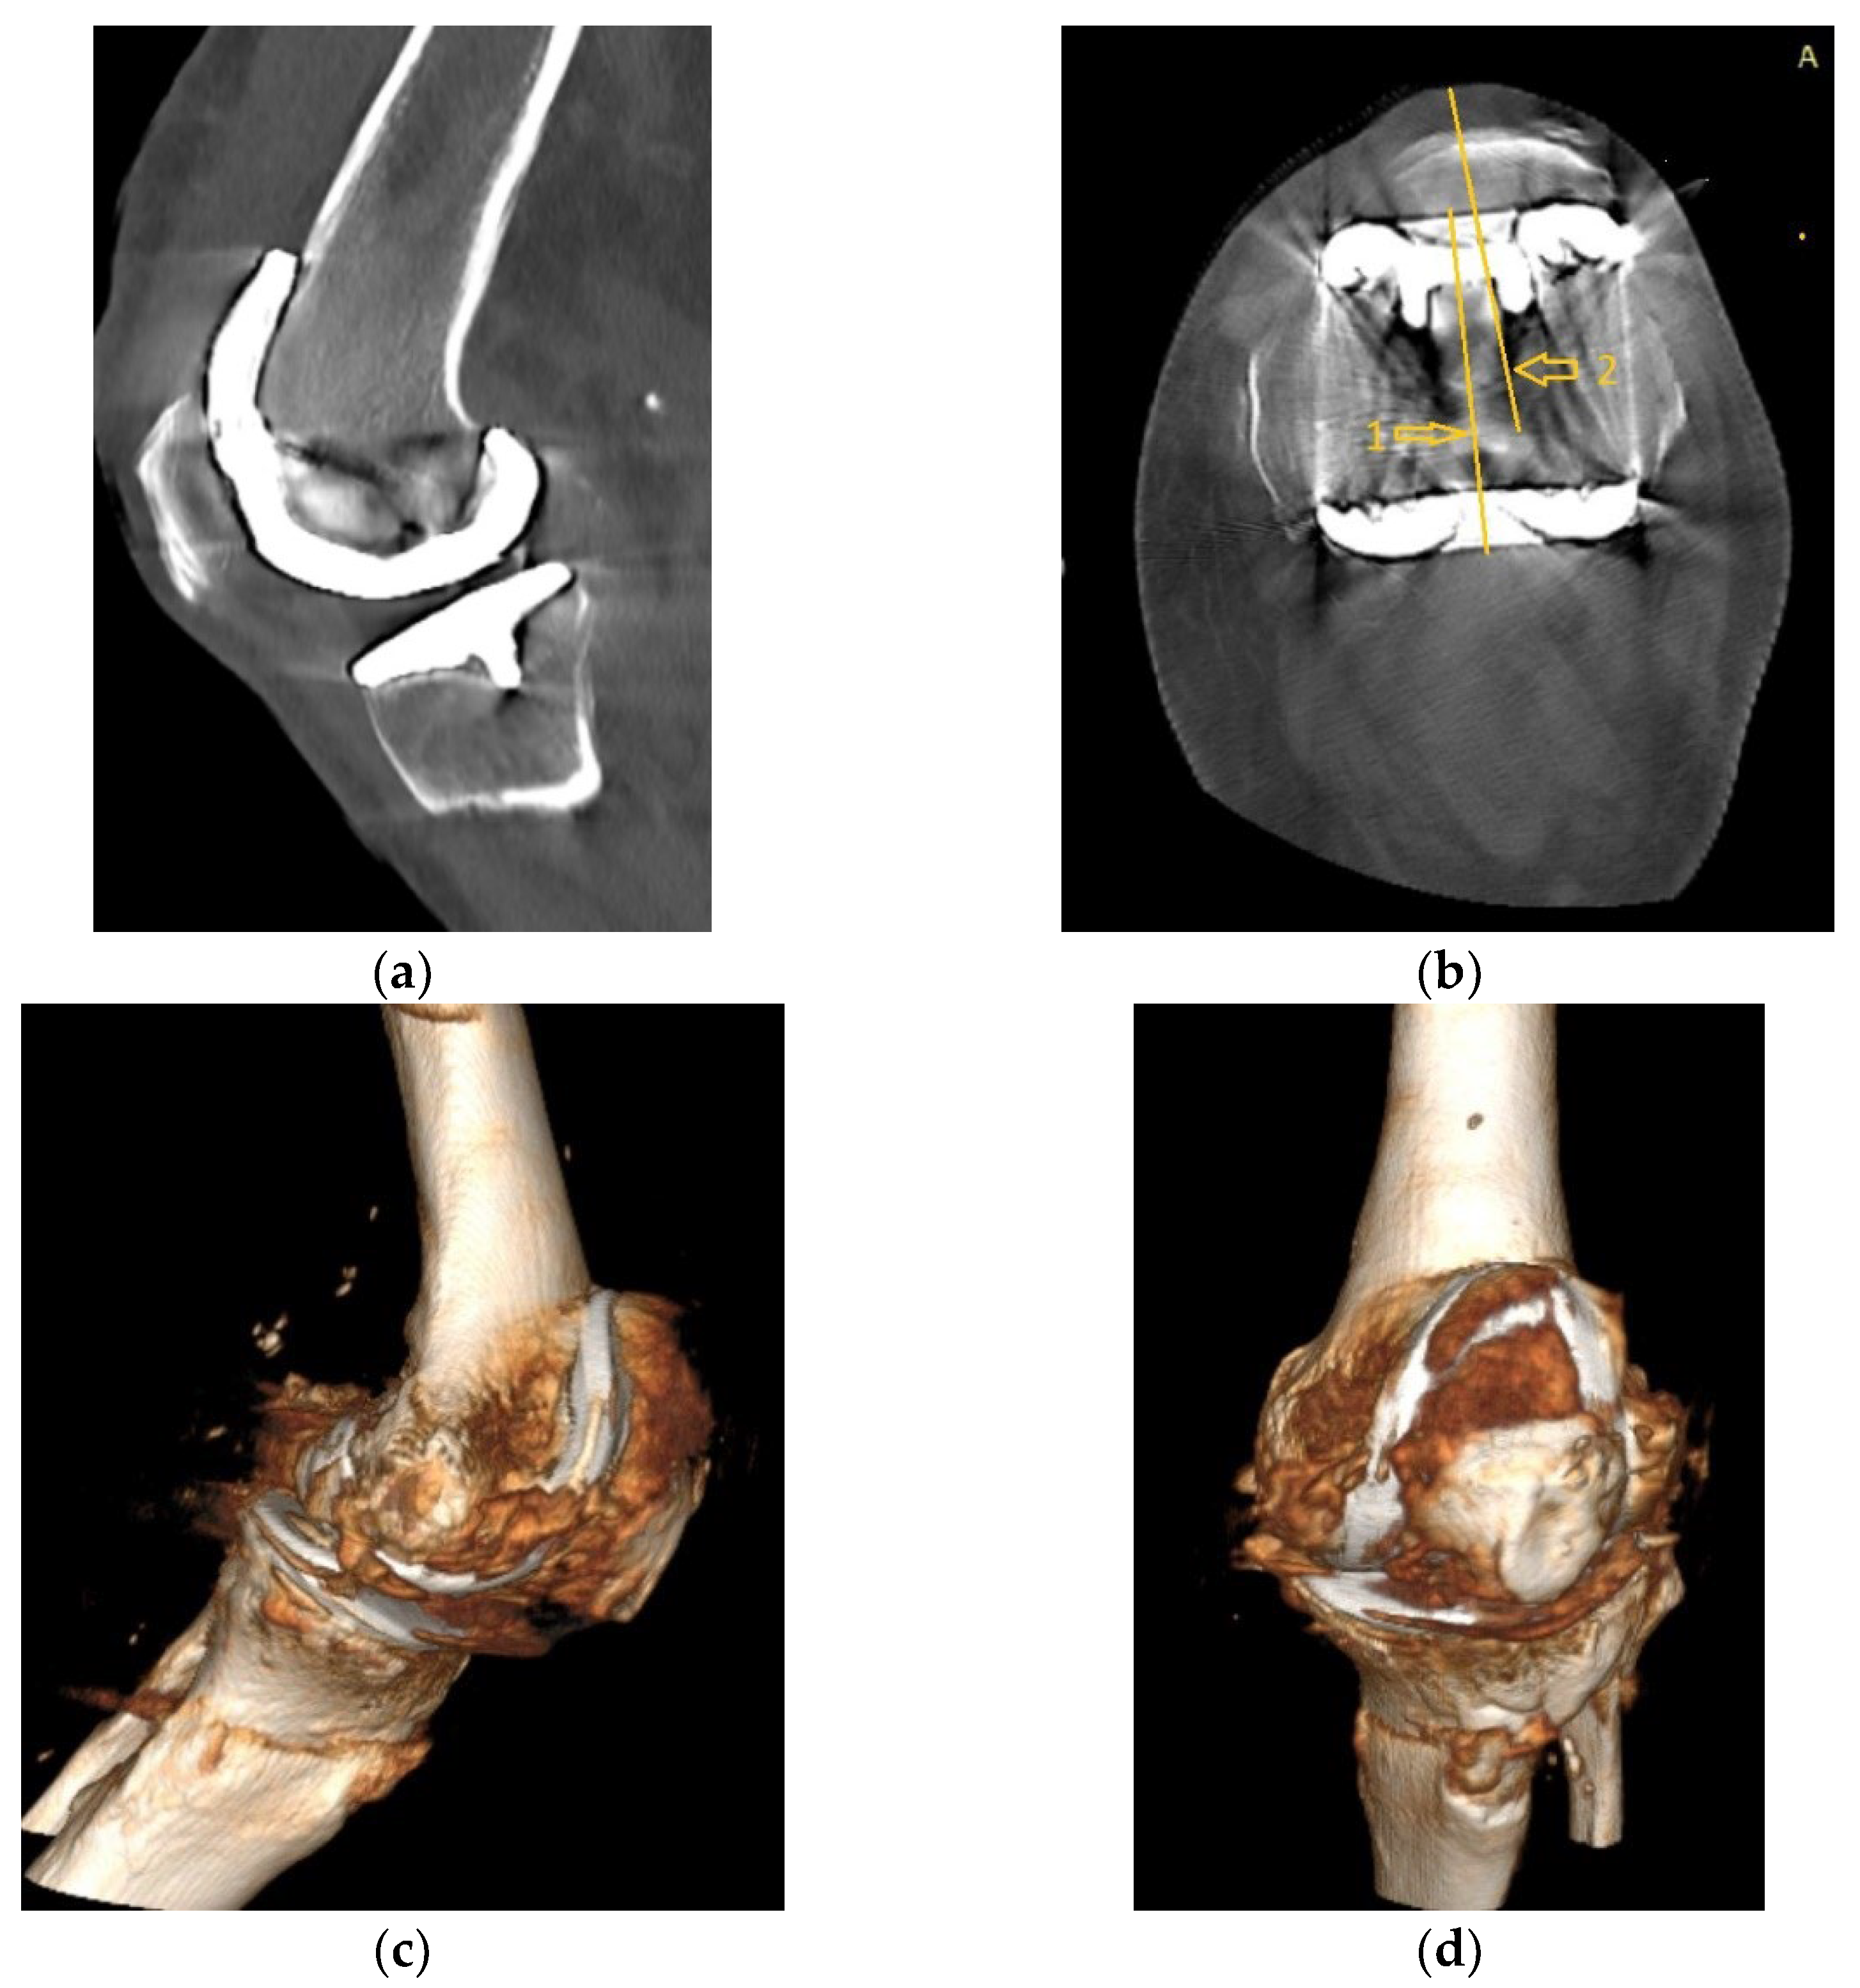

CT images, subject to artifacts generated by the implant, show patellar wear and peripatellar inflammatory phenomena (Figure 5).

Figure 5.

CT images: (a) Sagittal view showing patellar arthrosis, condensation of subchondral bone. (b) Axial view showing patellar arthrosis, deformation, and lateral subluxation (arrow) with (1) marking the femoral trochlear axis and (2) patellar axis; (c,d) CT 3D image, peripatellar inflammation.